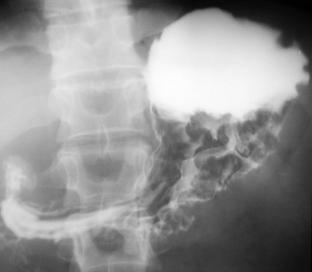

Lacuna este modificarea radiologica elementara care traduce existenta unui proces inlocuitor de spatiu dezvoltat in lumenul gastric de pe peretii stomacului. Din punct de vedere radiologic o lacuna inseamna o lipsa de opacifiere a unei portiuni din aria de proiectie a organului.

Unei lacune i se descriu numarul, forma, dimensiunile, localizarea, contururile si structura. Pentru a incerca o standardizare a interpretarii imaginii radiografice necesara studiului si pentru o diferentiere fata de lipsurile de umplere datorate hipertrofiei de tip polipoid a pliurilor, in analiza s-a considerat ca lacuna, un defect de umplere cu diametrul minim de 2cm.

Fig. 36 - imagine lacunara cu caractere maligne localizata la nivelul antrului

Din totalul celor 38 de cazuri studiate, 16 au prezentat imagini lacunare realizand un procent de 42,10 % . Repartitia acestor cazuri in functie de tipurile histologice de limfom este prezentata in tabelul urmator fig. 37).